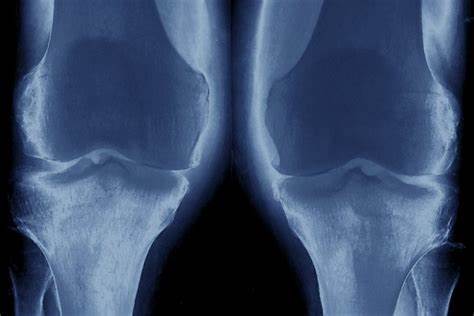

我们先来了解一下膝关节置换这个手术。

其实这个手术已经发展了很多年了,是非常成型的手术,目的就是为了解决那些由于骨关节炎,类风湿关节炎等疾病,常年经受着关节疼痛,严重影响生活质量的患者的痛苦。

我们就拿骨关节炎来举例,常年受骨关节炎困扰的患者,关节内的软骨已经磨损消失殆尽了,每天只要活动关节就会骨头磨骨头,那能不疼吗?严重的患者甚至不活动的时候,关节也会出现明显的疼痛,情况我们叫静息痛,另外很多患者还会出现明显的夜间痛,严重影响患者的睡眠质量,长期处于这样的状态,很多患者情绪也会出现明显的改变,比如出现焦虑症、抑郁症

再比如类风湿关节炎的患者也有类似的病情进展过程,类风湿滑膜慢慢的会将膝关节内的软骨侵蚀掉,关节会明显的变得狭窄,之后会慢慢形成广泛的粘连,患者的关节功能会有明显的障碍,而且还会有难以忍受的疼痛,很多患者会因为这种问题致残。